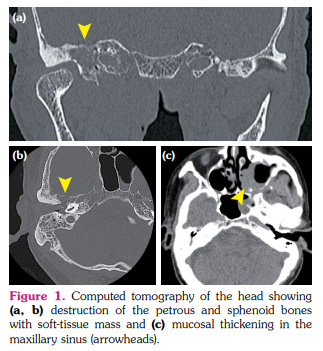

An 80-year-old man with a history of diffuse large B-cell lymphoma (DLBCL) presented to the otolaryngology department due to hearing loss and fullness in the right ear. He was diagnosed with primary testicular DLBCL five years earlier, but complete remission was sustained after treatment. Computed tomography identified a soft-tissue mass in the right middle ear and mastoid cells, along with destruction of the petrous and sphenoid bones with soft-tissue mass and mucosal thickening in the maxillary sinus (Figure 1a-c). A weakly positive result was obtained for serum proteinase 3-anti-neutrophil cytoplasmic antibody (PR3-ANCA), at 5.2 IU/mL. The patient was referred to our department on suspicion of granulomatosis with polyangiitis (GPA) and otitis media with ANCA-associated vasculitis (OMAAV). He showed no other symptoms suggestive of systemic vasculitis, and serum soluble interleukin-2 receptor was slightly elevated to 643 U/mL (normal: <610 U/mL). The T2-weighted magnetic resonance imaging (MRI) showed signal hyperintensity in the right mastoid, suggesting mastoid effusion (Figure 2a). However, contrast-enhanced MRI revealed enhancement around the mastoid cells and cranial base and nodules in the maxillary sinus (Figure 2b, c). Diffuse large B-cell lymphoma was diagnosed from biopsied mucosa in the maxillary sinus, with no findings of granuloma or vasculitis.